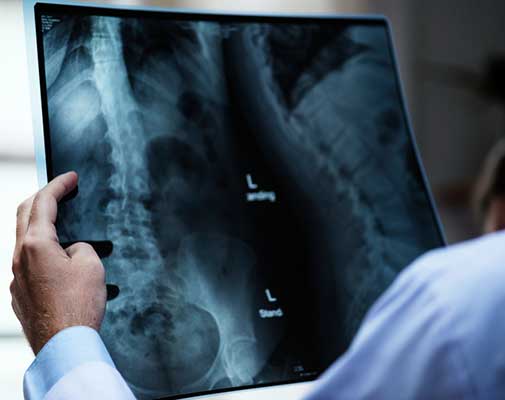

Omurganın ön ve arkadan bakıldığında 8 - 10 derece üzerindeki sağ veya sol tarafa olan eğriliği ile buna eşlik eden, kendi ekseni etrafındaki dönme hareketinin (rotasyon ) oluşturduğu bir şekil bozukluğudur. Skolyoz omurga deformiteleri içerisinde en sık karşılaştığımız ve ilerleyen evrelerde ciddi duruş bozukluklarına neden olan üç boyutlu bir omurga deformitesidir.